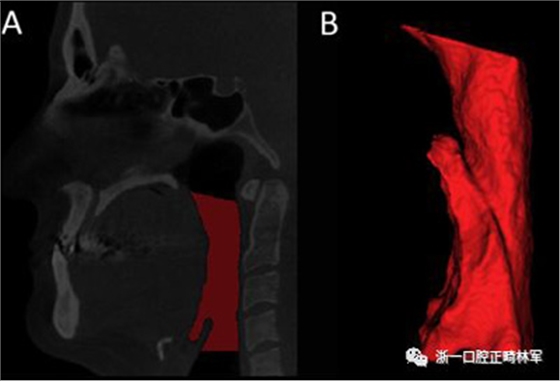

咽腔體積(PS體積)的分析是從三維模型進(jìn)行的。三維模型的重建采用軟件Insight ITK-SNAP(版本2.4.0; Cognitica,Philadelphia,Pa)的半自動(dòng)分割模式建立,該模型以立方毫米測(cè)量結(jié)構(gòu)的體積。本研究中測(cè)量的體積對(duì)應(yīng)于口咽和下咽部之間的聯(lián)合。為此,我們按照Park等描述的解剖學(xué)定義確定了從后鼻棘到第一頸椎的最低點(diǎn)的上部參考線,以及在垂直于內(nèi)側(cè)矢狀面的第四頸椎最低點(diǎn)上描繪的下部參考線(圖5)。

圖5.A,使用文本中描述的參考點(diǎn)對(duì)咽腔進(jìn)行分割(紅色); B,口咽和下咽部之間的聯(lián)合體積。